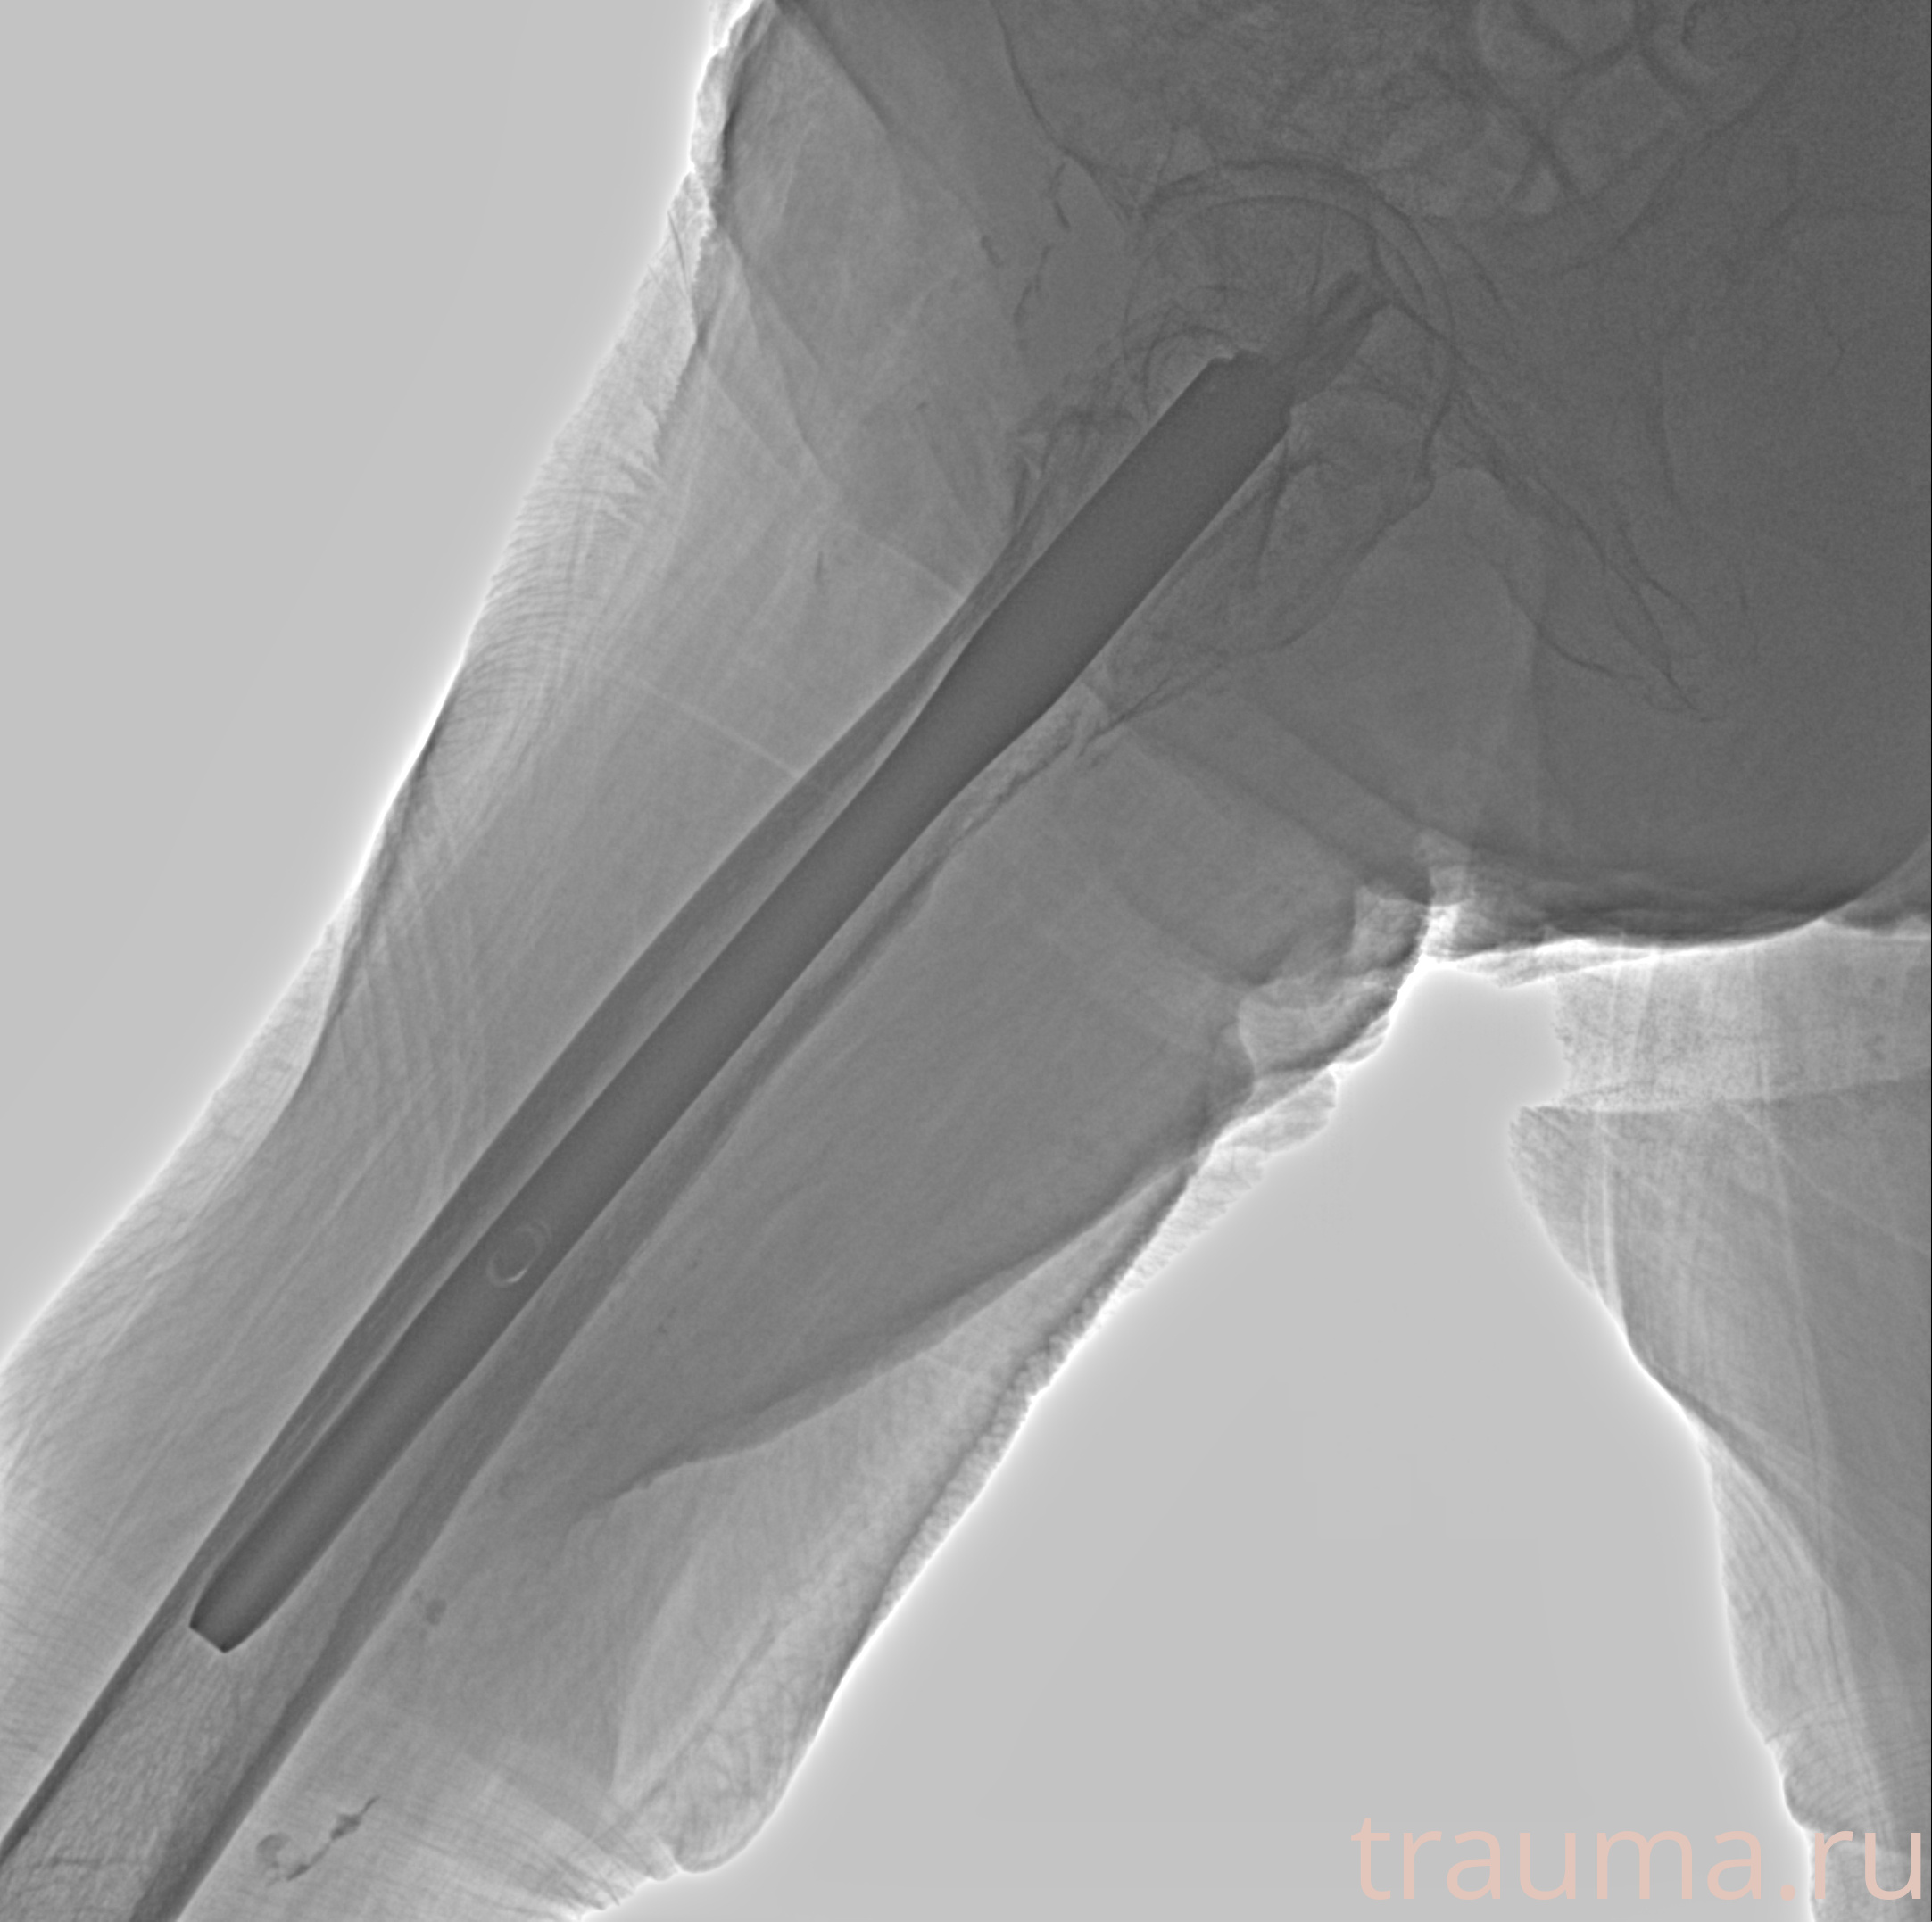

Рентген на дому: по вашему адресу приезжает врач-рентгенолог, травматолог-ортопед с мобильным рентгеновским аппаратом, проводит диагностику травмы или заболевания, делает необходимые рентгенограммы, дает рекомендации по дальнейшему лечению. Получить качественные снимки в домашних условиях возможно благодаря уникальной методике, разработанной МосРентген Центром для института  Склифосовского

при переломе шейки бедра и пневмонии от компании МосРентген Центр - партнера Института имени Склифосовского